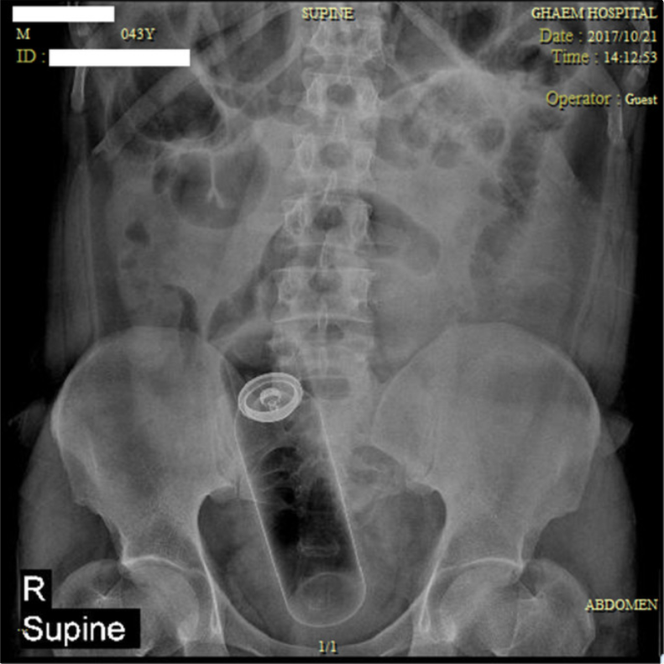

Quelques mois passent. Cette fois, notre homme a introduit dans son rectum une balle en caoutchouc d’environ 9 cm de diamètre, coincée à 6 cm de la marge anale. La radiographie confirme la localisation. Le bloc opératoire rouvre ses portes et la main du chirurgien fait ce qu’elle sait faire. L’histoire se termine à nouveau sans complication.

En 2021, dernier épisode connu : une balle souple en plastique d’environ 10 cm, visualisée à l’imagerie, est extraite, toujours par voie transanale. Il faudra cependant la dégonfler pour qu’elle accepte de faire le chemin inverse, dans un scénario désormais bien rodé.